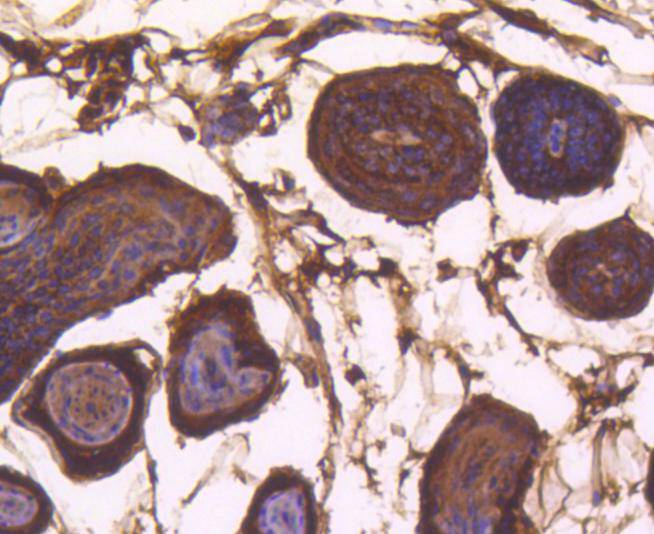

Immunohistochemical analysis of paraffin-embedded mouse prostate tissue using anti-Bax antibody. Counter stained with hematoxylin.